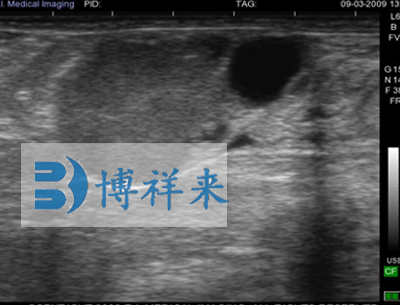

兽用B超影像图像